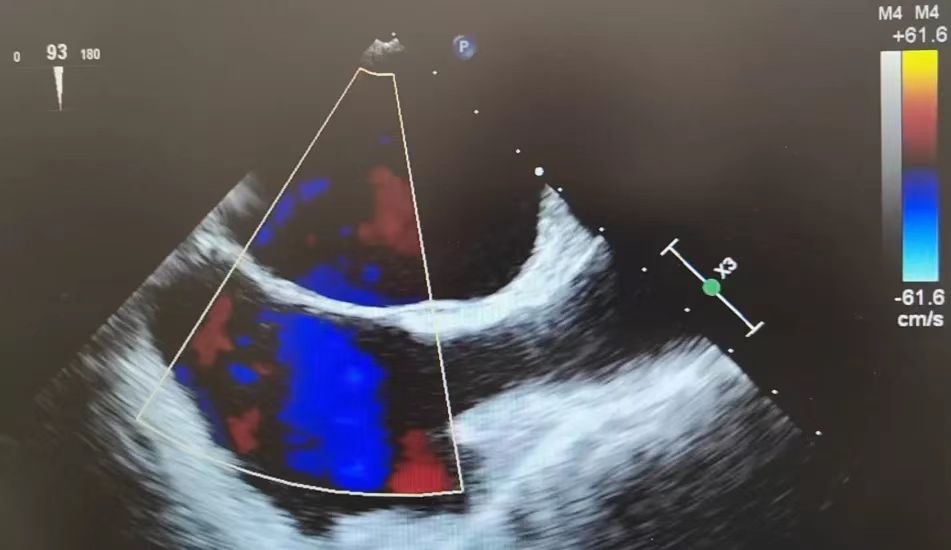

▲经食道超声几乎可以实现360°无死角地检查

经食道超声心动图

术前检查患者左心耳有无血栓